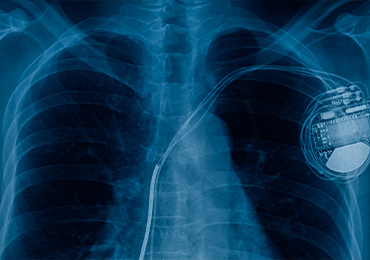

Die Markteinführung eines Medizinprodukts erfordert weit mehr als nur Innovation – sie bedeutet, sich durch ein komplexes Umfeld aus Regularien, Audits und klinischen Risiken zu bewegen. Ob bei der ersten Zulassung oder im Rahmen der Marktüberwachung: Der Druck, internationalen und sich ständig weiterentwickelnden Standards gerecht zu werden, ist hoch. Was Sie brauchen, ist ein Partner, der Herausforderungen frühzeitig erkennt, Wissenslücken schließt und Ihr Produkt sicher, effizient und erfolgreich durch jede Phase seines Lebenszyklus begleitet.